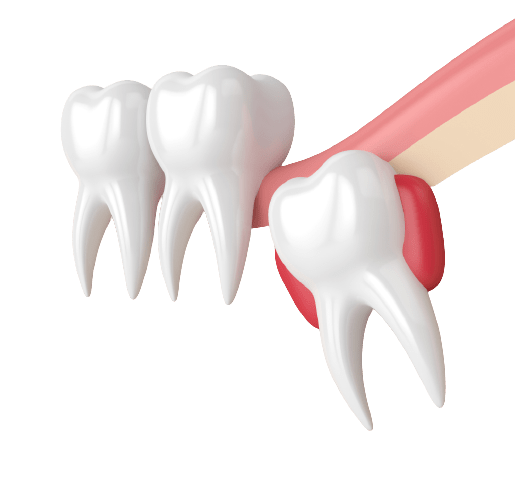

במקרים מסוימים יש צורך בהליך של עקירת שן בינה בולטת או חבויה כדי למנוע פגיעה בשיניים סמוכות עקב לחץ.